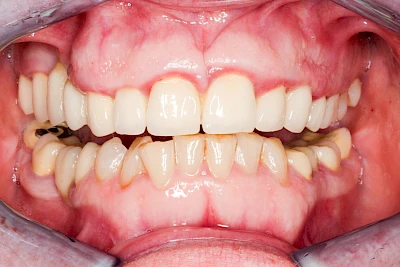

Ist zunächst nur das Zahnfleisch von der Entzündung betroffen, spricht man von Gingivitis. Später, wenn auch der Knochen um die Zähne herum entzündet ist, spricht man von einer Parodontitis. Bei der Parodontitis wird der Knochen nach und nach abgebaut und das Zahnfleisch zieht sich zurück. Die Zahnhälse und Zahnwurzeloberflächen liegen mehr und mehr frei. Die Zähne werden zunehmend lockerer und fallen schließlich aus.

Gingivitis & Parodontitis: Stadien